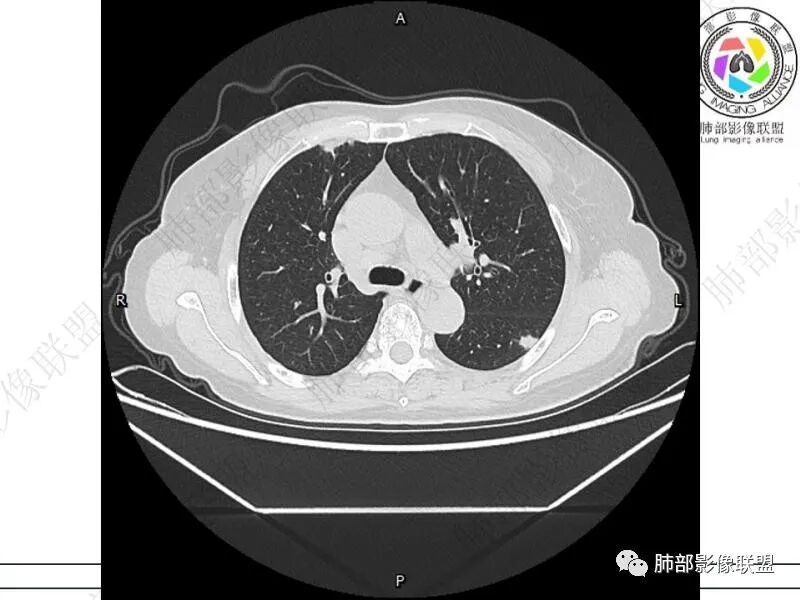

丽:双肺下叶胸膜下多发片状高密度影,边缘模糊不清,内可见支气管穿行,病变长轴平行于胸膜,考虑感染性病变,隐球菌

媛:肠癌术后,免疫力低下。两肺胸膜下结节及实变影,实变影长轴平行于胸膜,密度均匀,边界偏清,周围有晕征,短期复查进展,虽隐球菌荚膜抗原检测阴性,还是考虑隐球菌,鉴别OP

谢加平:结肠癌术后史,两肺胸膜下多发结节及斑块实变病灶,实边边界平直征(亚急性和慢性病变过程),双肺下叶后基底段胸膜下为甚,与胸膜平行特点,见支气管充气征,边缘模糊的GG0,首诊2022年11月18日肺部CT,与治疗11月28日对比,病灶未吸收,双肺下叶胸膜下病灶有侧向融合特点,综合分析符合炎性肉芽肿,隐球菌感染。

良孑:两肺胸膜下多发相类似结节,部分结节有晕及晕中软毛刺,部分结节侧向融合,长轴与胸膜平行,结节边缘可见刀切征,右半结肠癌术后免疫力低下,综合考虑支持隐球菌

老年女性,结肠癌术后。两下肺胸膜下为主片状实变,右下肺短期复查融合且病灶长轴平行于胸膜,实变内可见支气管充气征,边缘磨玻璃晕,另两肺内胸膜下散在数枚小结节状、楔形实性灶。考虑感染性病变,隐球菌可能,鉴别肺转移。

2.影像特征:双肺胸膜下多发实性结节、磨玻璃影及实变影,胸膜下优势分布、晕征、胸膜下脂肪间隙存在,部分病灶边界平直征,有侧向融合趋势。